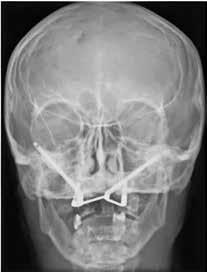

ÅR EN RODBEHANDLET TAND har nået et punkt, hvor tandsubstansen er stærkt reduceret pga. cuspisfraktur, caries, fyldninger eller som følge af endodontisk behandling (Fig. 1A og B), kan det være indiceret, at tanden genopbygges med stift, opbygning samt støbt restaurering (1-5). Førstnævnte for at opnå tilstrækkelig retention af opbygningen. Det er udbredt, at guttaperkafjernelse er mekanisk baseret med anvendelse af et roterende bor (Fig. 1C) (3,6). Boret placeres over rodfyldningen, hvorefter den koronale del samt noget af rodkanalvæggen fjernes mekanisk (4). Den mest apikale del af rodfyldningen bibeholdes, for at denne fortsat er tæt (2,3). En af udfordringerne ved en optimal guttaperkafjernelse samt stiftudboring er muligheden for at følge rodfyldningen uden at afvige fra rodkanalen (7,8). Perforation af tandroden kan ske ved ukorrekt vinkling (Fig. 1C og D), og risikoen forstærkes yderligere ved kraftigt reduceret tandsubstans i den cervikale del af kronen (9,10). Inspektion og belysning kan være besværliggjort, og endelig kan rodfyldningen være meget hård, hvilket komplicerer den taktile sansning under præparationen (9,11). Den utilsigtede vinkling af stiftudboringen, ultimativt rodperforationen,

Fig. 1. Radiologisk sekvens efter en rodperforation i forbindelse med en stiftpræparation i en underkæbemolar (-6). A. Røntgenbillede før rodbehandling. Rodkanalmorfologien viser, at den distale rod har to adskilte rodkanaler (pil). B. Rodbehandling afsluttet og kontrolleret. C. Initial mekanisk fjernelse af rodfyldning. D. Efter mekanisk fjernelse af rodfyldning ses en retningsafvigelse i forhold til den nederst beliggende rodfyldning. E. En midlertidig fyldning af rodkanalen viser rodperforationen (pil). Der er indhentet patientsamtykke til visning af røntgenbilleder.

Fig. 1. Radiologic sequence after root perforation in connection with mechanical preparation of a post in a mandibular molar (-6). A. Radiograph before the procedure. The morphology of the root canal shows that the distal root has two separate root canals (arrow). B. Procedure completed and controlled. C. Initial mechanical removal of root filling. D. After the mechanical removal of root filling the direction of the drill deviates from the lowest part of the root filling. E. A temporary filling of the root canal shows the root perforation (arrow). The pictures are used with the permission and consent of the patient.

kan forekomme for selv en erfaren tandlæge, da sågar et optimalt 2D-røntgenbillede ikke altid gengiver korrekt morfologi (11,12).